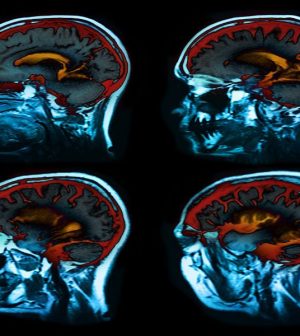

In separate studies of 30 additional patients and a group of healthy adults, Bernasconi’s team used MRI scans to see how brain activity patterns were related to presence hallucinations.